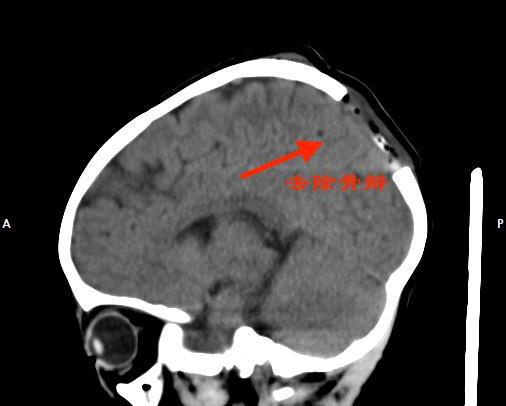

▲术前影像检查

我院神经外三科副主任杨宝应在查看薇薇的影像资料时,发现薇薇的右侧顶骨有一椭圆形骨质破坏,大小约为3X3cm²;缺损区边缘锐利清晰,与正常颅骨界线分明;已有软组织形成。杨宝应初步诊断是LCH。